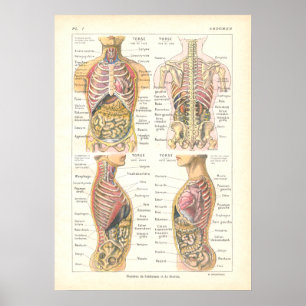

Viscera och buksmärtor Poster Fransk

Pris390,00 kr

Anatomi i mänskliga organ poster

Pris229,00 kr